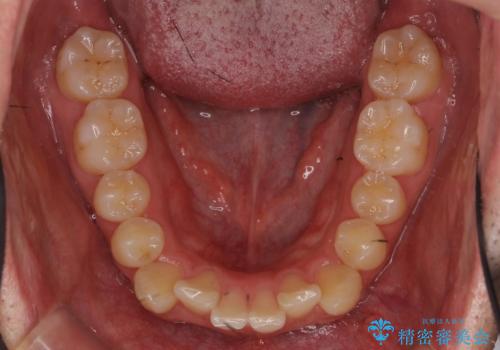

- 前歯のがたつきを主訴に来院。

歯を抜かずに、奥歯を後ろに下げ、歯の両側をわずかに削って並べました。

奥歯を後ろに下げるのに、上下左右に矯正用ミニスクリューを入れています。

そのまま並べると戻りやすいのと、口元が出てしまうためです。

歯のがたつきがなくなると、歯ブラシがしやすくなり、茶色いステインも付きにくくなります。